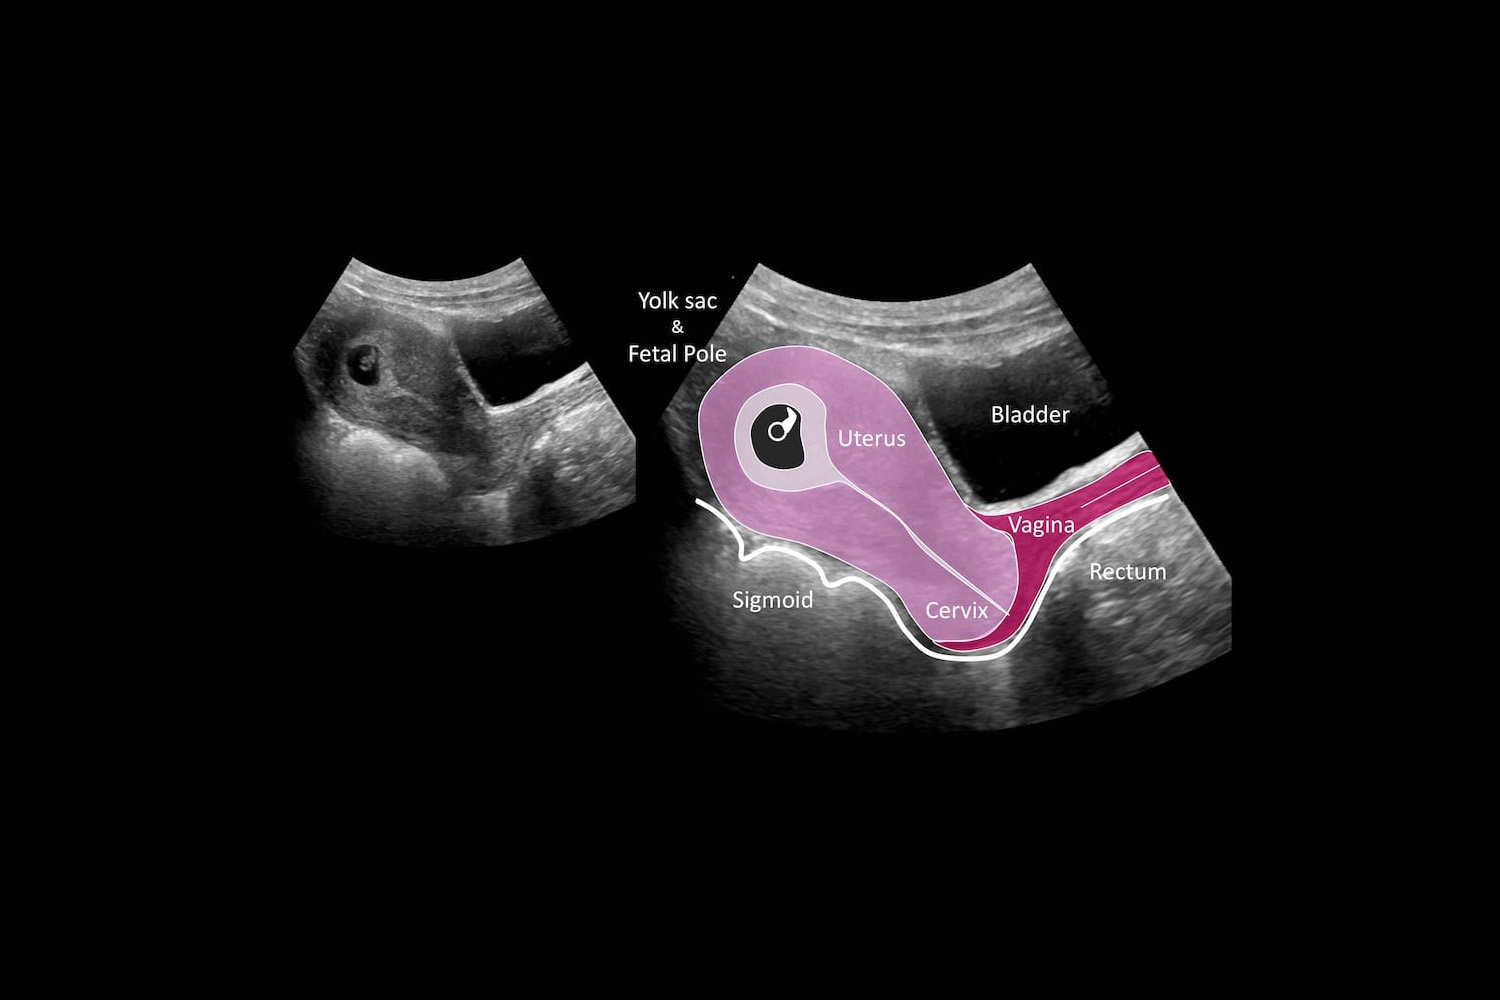

Free Ultrasounds | Wednesday (10:00 AM — 5:00 PM) | Friday (1:00 PM — 5:00 PM)

We provide free Pregnancy And Ultra Sounds Tests

Ultra Sound?